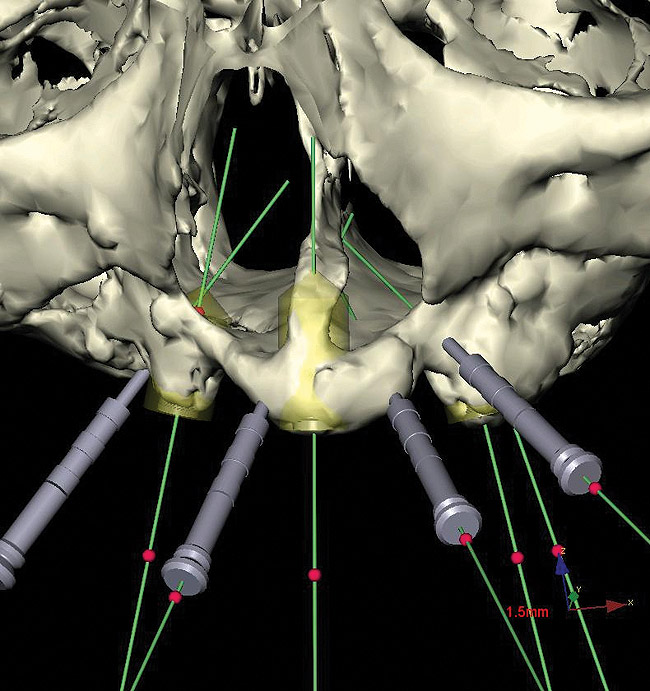

Panoramic and periapical radiographs are 2-dimensional (2-D) representations of a patient’s 3-D anatomy. Differences in radiographic machines and techniques can lead to image distortion, such as elongation and shortening of anatomy. Accurate evaluation and measurement of the relationship between the mental nerve, inferior alveolar nerve (Figure 4), or nasopalatine/incisive nerve, and the planned implant position can best be determined and planned by a 3-D evaluation of the anatomy as related to the planned restoration.3,30 Implant placement in patients in whom there is a question of nerve or sinus proximity is most accurate using “virtual” treatment planning and placement using CT-generated guides, thus minimizing potential patient morbidity. Technologies such as “all-on-four,” which is designed to maximize the intra-arch spread of implant platforms while avoiding the mandibular nerve and maxillary sinus, are excellent indications for CT-guided implant surgery (Figure 5 and Figure 6).

Figure 19  Virtual implant placement, iliac crest bone graft reconstruction secondary to ameloblastoma resection, mandible.

Figure 19